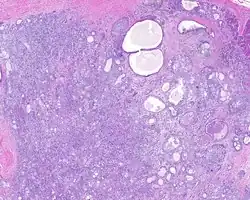

When reviewed by a pathologist, the findings are quite similar to fibrocystic changes of the breast, although they are different enough, that it is now recognized to actually represent a true neoplasm (clonal proliferation) through various studies.[5] Specifically, the lesions are usually well-circumscribed, containing lobules of haphazardly arranged ducts, myoepithelial cells, and acini that have abundant sclerosing or hyalinized fibrosis. Apocrine change is quite common in the ductal cells.[6] The ducts range from small ductules to cystically dilated spaces (more than 4 striated duct-widths across), often containing products of secretion or reactive histiocytes. A very curious and characteristic finding in all of the lesions is the presence of bright pink (eosinophilic) acinar granules (which are altered zymogen).